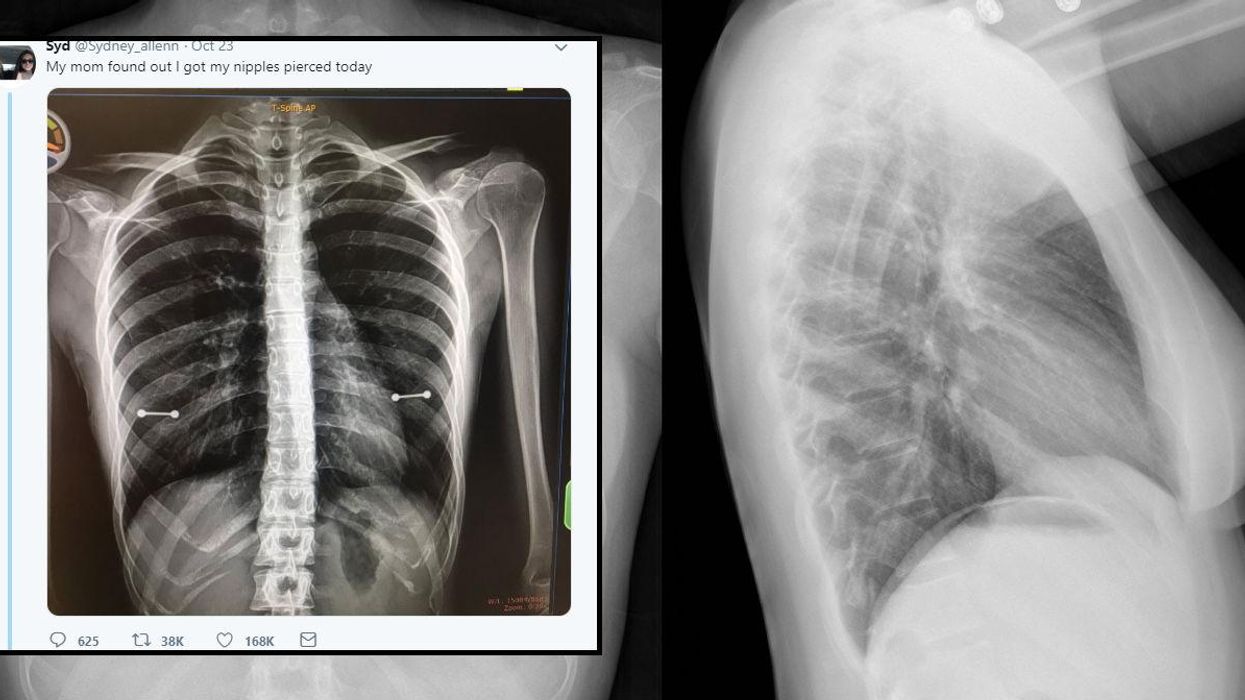

Sydney Allenn uploaded a photo of an X-ray image and captioned it:

My mom [sic] found out I got my nipples pierced today.

Twenty-year-old Sydney, from Clearwater Florida secretly got her nipples pierced back in June as a birthday gift from her sister.

And she kept it for a few months, but a check-up at the hospital changed that. She has syringomyelia, which is a rare condition that builds up spinal fluid in the spinal cord.

My mom [sic] saw my piercings as soon s the X-ray popped up and the doctor and I started laughing hysterically.